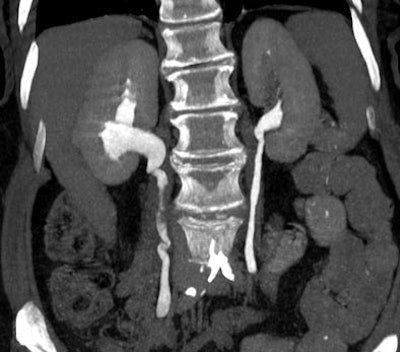

| Transitional cell cancer of the right upper ureter. Above, axial excretory-phase CT showing soft-tissue filling defect in the upper third of the ureter. Below, coronal thin-slab maximum intensity projection showing characteristic signs of ureteral transitional cell carcinoma. Images courtesy of Dr. Nigel Cowan. |